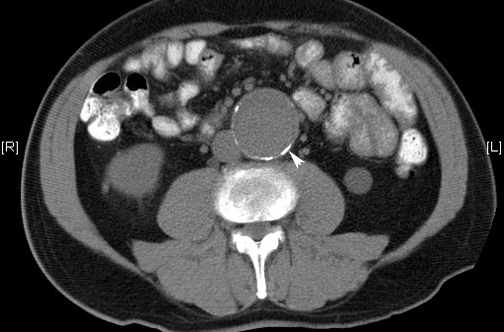

Aneurismas de aorta abdominal: más cirugías y menos mortalidad en EEUU

La tasa de cirugías para reparación electiva del aneurisma abdominal en EEUU duplica la de Inglaterra, pero la mortalidad por rotura aneurismática es tres veces menor. New England Journal of Medicine, 24 de noviembre de 2016